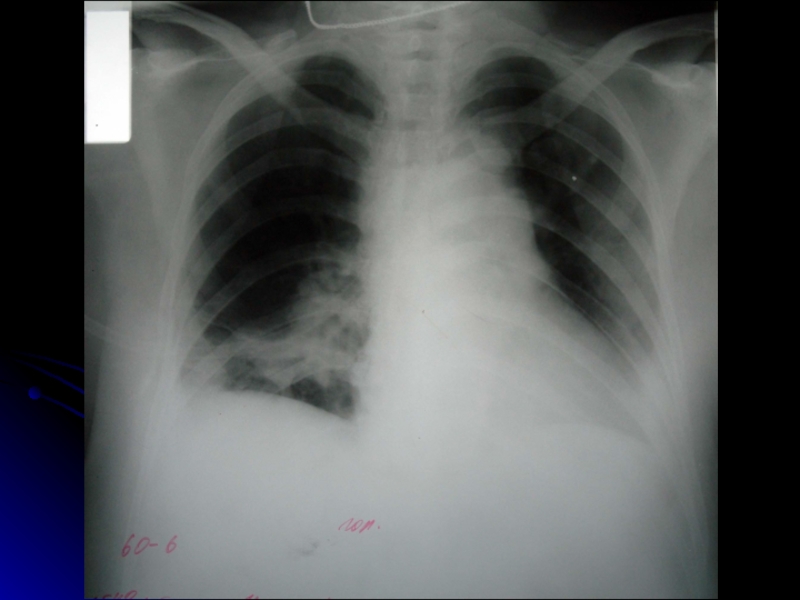

Слайд 18РЕНТГЕНОЛОГИЧЕСКИЕ ПРИЗНАКИ ТЭЛА (нарушения кровотока в легочных артериях, инфаркт легкого)

• симптом Вестермарка

– локальное обеднение сосудистого рисунка (просветление легочного поля на ограниченном участке);

• резкое расширение корня легкого, его «обрубленность», деформация;

• появление дисковидных ателектазов в легких, часто предшествующих развитию инфаркта в данной зоне;

• инфильтрация легочной ткани, выявляемая не ранее 2 дня заболевания всего лишь у 10% больных – обычно расположенная субплеврально, округлой или неправильной, а в ряде случаев клиновидной формы, обращенная основанием к периферии (инфаркт легкого);

• высокое стояние диафрагмы на стороне поражения;

• выбухание легочного конуса – второй дуги по левому контуру сердечной тени (расширение ствола легочной артерии), расширение тени сердца за счет правого предсердия и правого желудочка;

• расширение тени верхней полой вены; вена считается расширенной при увеличенном более 3 см расстоянии между линией остистых отростков и правым контуром средостения.

Почти у трети больных рентгенологические признаки эмболии отсутствуют.